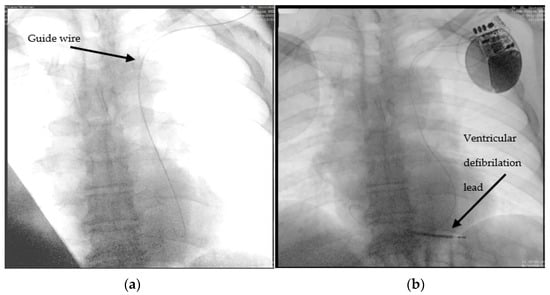

2.2. Case 2. (Type IIIa)